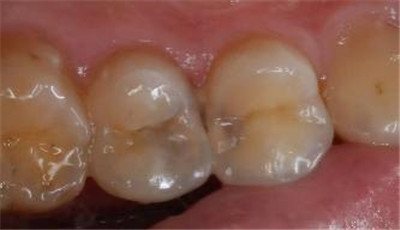

虽然绝大多数情况是慢性龋病的最终表现,但也有其他可能性,但相对少见:

1.急性龋(猛性龋):

这是一种发展非常迅速的龋病。常见于:

唾液分泌少的人(如服用某些药物、接受头部放疗后)。

饮食习惯极差的人(频繁摄入高糖饮料、零食)。

婴幼儿奶瓶龋。

即使发展快,它也需要几周或几个月的时间,而非真正的一夜之间。